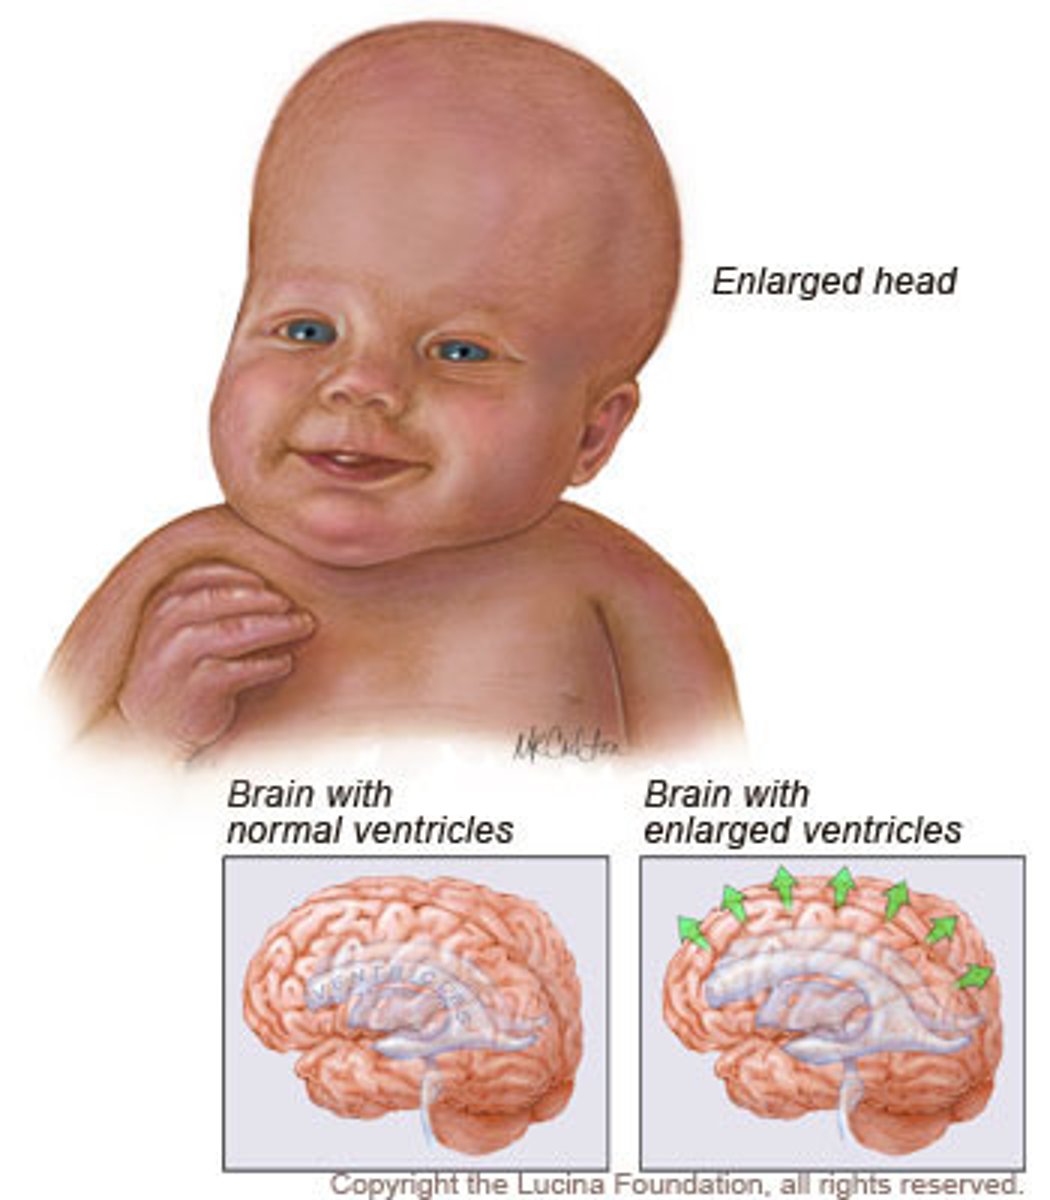

The opening of the neural tube become

Ventricles

4 Chambers within the brain,

Filled with Cerebrospinal Fluid,

Continuous with each other and with the central canal of the spinal cord

4 Chambers within the brain,

Filled with Cerebrospinal Fluid,

Continuous with each other and with the central canal of the spinal cord

Cerebrospinal Fluid (CSF)

1) Formed by choroid plexus in each ventricle.

2) Similar to blood but no red blood cells and much lower protein level.

3) Supplies nutrients and forms protective fluid cushion that gives buoyancy to CNS structures:

-Reduces brain weight by ~97% and prevents it from crushing under its own weight (very delicate)

4) Circulated in subarachnoid space, ventricles, and central canal (facilitated by ependymal cells that line each of these areas)

Ventricles

1) Right & left lateral ventricles:

-Anterior, Posterior & inferior horns

2) 3rd Ventricle, Cerebral aqueduct, 4th ventricles

4) Apertures (Narrow openings) into subarachnoid space of spinal cord

Hydrocephalus

water on the brain